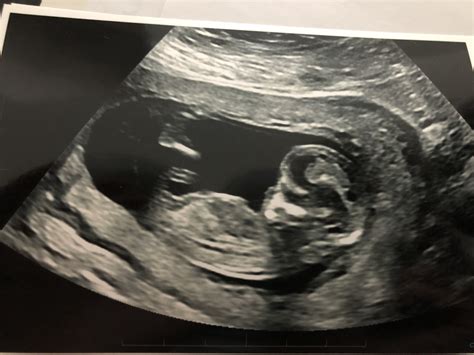

Common Findings and What They Mean

The 12 week ultrasound can reveal various findings, some of which may require further investigation. Here are some common findings and their implications:

• Normal Findings: Most 12 week ultrasounds reveal normal findings, indicating that the baby is developing as expected. This includes a normal CRL, NT measurement, and visible anatomy.

• Abnormal NT Measurement: An increased NT measurement may indicate a higher risk of chromosomal abnormalities or other genetic conditions. Further testing, such as amniocentesis or chorionic villus sampling (CVS), may be recommended.

• Absent Nasal Bone: The absence of the nasal bone can be associated with an increased risk of Down syndrome. Additional testing may be advised.

• Heartbeat Abnormalities: An abnormal heartbeat may indicate potential cardiac issues. Further evaluation by a specialist may be necessary.